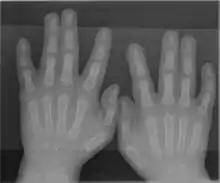

A rare anatomical variation affects 1 in 500 humans, in which the individual has more than the usual number of digits; this is known as polydactyly. A human may also be born without one or more fingers or underdevelopment of some fingers such as symbrachydactyly. Extra fingers can be functional. One individual with seven fingers not only used them but claimed that they "gave him some advantages in playing the piano".[15]